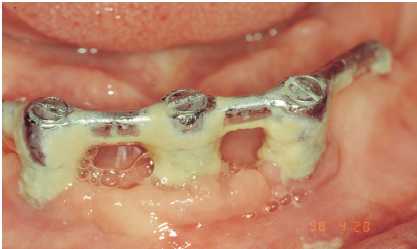

Figuras 2a y 2b. Adiestramiento en la clínica con el

paciente de la utilización de superflos y cepillos interproximales